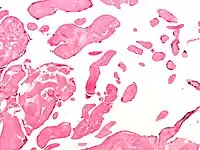

Papillary fibroelastoma are typically found and accurately diagnosed by imaging. The diagnosis is confirmed by pathology. Histologically, papillary fibroelastomas have branching avascular papillae, composed of collagen, that are covered by endothelium.